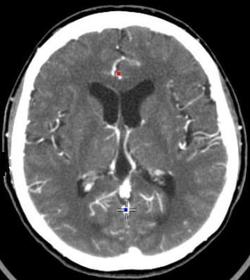

What is a CAT / CT scan ? Computerised Axial Tomography combines a series of X-ray images taken from different angles and uses computer processing to create cross-sectional images, or slices, of the bones, blood vessels and soft tissues inside your body. The amount of X-rays absorbed is dependant on the density of the tissue. An image can be built up based on amount of absorption / transmission

What are the negatives of CT / CAT scans? - Harmful, cannot x-ray someone without a valid reason - Cannot give someone multiple x-rays as risk increases